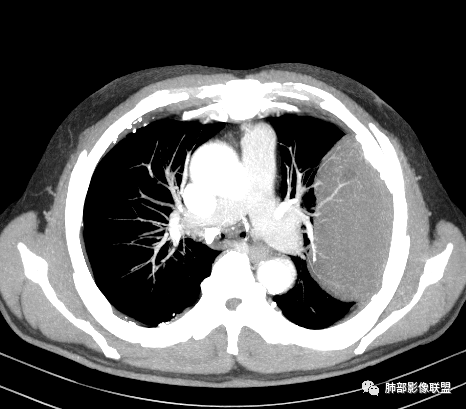

我要修正一下观点了:仔细看了视频,肿块占位效应明显,对周围血管,支气管有推挤,增强后强化不明显,NSE增高,半年体重下降25公斤,虽然有内部支气管扩张,血管漂浮,边界清楚支持淋巴瘤,但强化太低,膨隆,占位推挤太明显(淋巴瘤一般没有这么明显的占位效应),胸膜关系有载桩,恶病质明显(乏力,半年体重下降了25公斤),NSE也明显增高,就不支持淋巴瘤了。还是考虑外朝内的恶性肿瘤,间质来源的肉瘤伴有神经内分泌分化或者大神泌。

不支持淋巴瘤的有四点:1、对周围血管支气管推挤明显。2、胸膜有栽桩,3、强化太弱(淋巴瘤一般还是中度以上甚至高度强化多见),4、NSE升高明显,体重下降太明显。

腺癌一般不会有这么明显的推挤作用的。

我再建一下血管。支气管进入,但是近端推移,堵塞

肺动脉推移为主,边缘部分进入

回头看,内部支气管近端其实不连续,伴随肺动脉不存在

5)肿瘤强化方式:肺部恶性肿瘤强化程度与其血供丰富程度相关,血供丰富多强化明显,反之则较差。由于PSC 周边实性部分富血供及内部黏液变性、坏死,增强后肿块多数呈轻-中度边缘环形强化或不均匀小斑片状强化。国外学者对照病理发现肿瘤细胞或胶原组织增强扫描时强化,无强化的低密度区代表了黏液样变性区和出血坏死区。